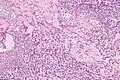

HCCC consist of cells with abundant clear cytoplasm, arranged in cords, trabeculae or clusters in a hyalinized stroma.[3] Nuclear pleomorphism is usually minimal and mitoses are infrequently seen.[2]

Owing to their glycogen content, which explains the "clear" appearance under the microscope, tumour cells stain with PAS. Immunostains for S100 and smooth muscle actin (SMA) are typically negative, but positive for cytokeratins and epithelial membrane antigen (EMA).

Very high mag.

Very high mag.